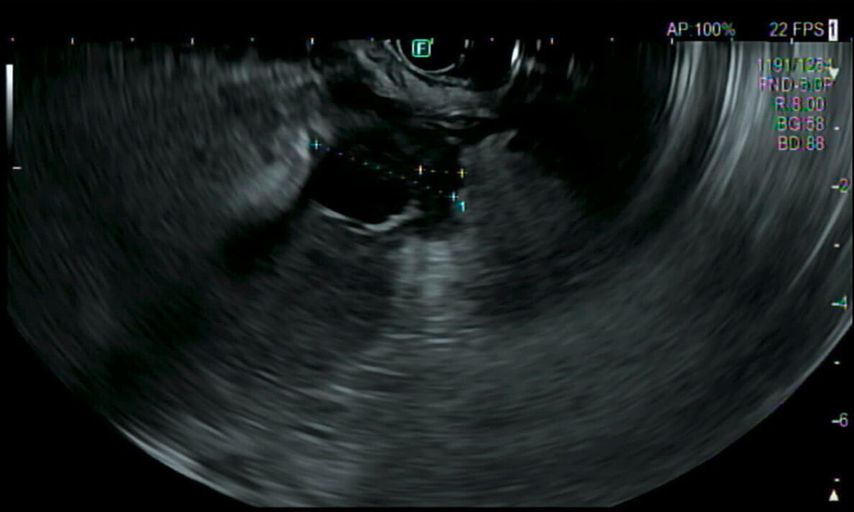

Eine Gastroskopie unter Intubationsnarkose wird angeschlossen (Abb.2). Gastroskopisch ist der Magen leer, die Schleimhaut adäquat durchblutet, ohne Ulzerationen oder malignomsuspekte Areale. Die einzige Auffälligkeit: Der Magen entfaltet sich nicht gänzlich, und zwar aufgrund einer submukös liegenden, verdrängenden Raumforderung im Bereich der Magenvorderwand. Aufgrund der Raumforderung kann der Pylorus nicht eingesehen werden.

Im Rahmen der Narkose wird eine Sonografie des Abdomens ergänzt, in der sich nun der Verdacht bestätigt, dass die große Fluidokollektion nicht im Magen, sondern intramural in der ventralen Magenwand liegt.